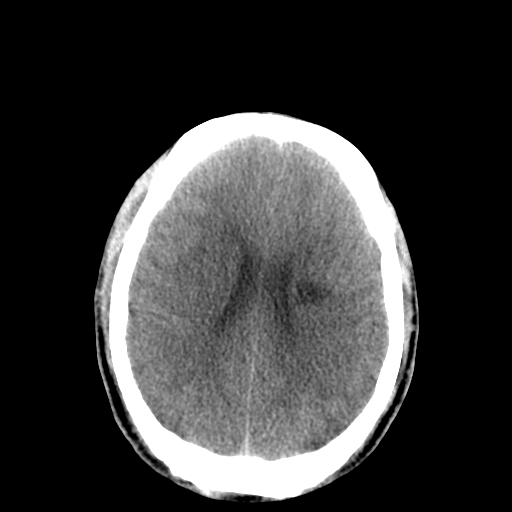

以下是引用李衡钧在2008-9-18 17:37:00的发言:[br]脑质内见两个低密度灶,其内见点状高密度。[br]考虑脑囊虫。建议增强或进一步检查确诊。

以下是引用chmh在2008-9-18 18:45:00的发言:[br]考虑脑囊虫病可能性大,建议行ct增强检查及血清和脑脊液囊虫补体结合试验.